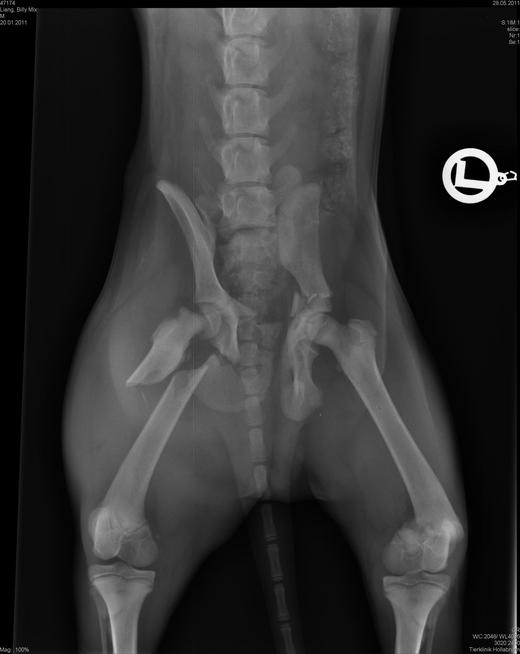

狗才四個月太小,因此要分兩次開刀,第一天是開後面兩條骨折的腿,大腿上各放了兩個固定鐵片.

骨盆腔裡面放了特殊的伸縮螺絲;第四天狗才能出院.